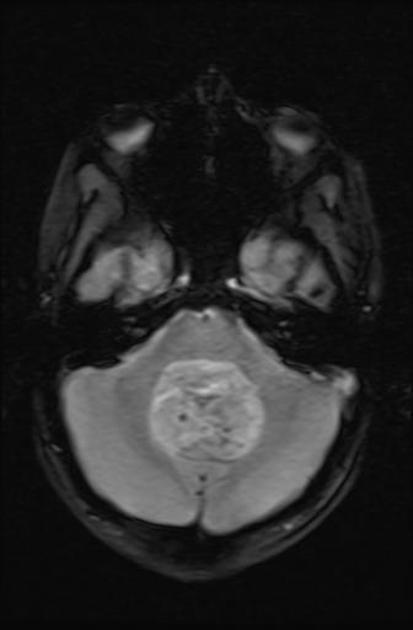

A comprehensive history and physical and MRI imaging of the CNS axis is required. The MRI typically shows a posterior fossa mass which is hypointense to iso-intense on T1 series. It is hyperintense (white) to white matter on T2 series. T1/gad shows heterogeneous enhancement and CT shows calcifications. Once the imaging series is obtained, CSF sampling (particularly in anaplastic Grade III) should be obtained to rule out leptomeningeal seeding. CSI may be required in anaplastic ependymoma.

Ependymoma Gradient Echo

Ependymoma T2